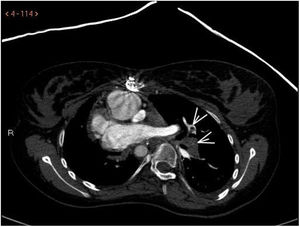

Niña de 16 años con antecedentes personales de cardiopatía congénita compleja que precisa fístula sistémico-pulmonar derecha, y a los 6 años de edad anastomosis cavo pulmonar bilateral (intervención de Glenn). Ingresa en la UCI pediátrica por dificultad respiratoria e hipoxemia severa. Ante la sospecha de TEP se inicia tratamiento con heparina sódica y 24h más tarde por empeoramiento clínico progresivo se realiza nuevo angio-TAC, donde se visualiza trombo en la comunicación de VCSI con arteria pulmonar izquierda compatible con tromboembolismo masivo de pulmón izquierdo (fig. 1, ver flechas). Se inicia tratamiento con activador recombinante tisular del plasminógeno (rTPA), bolo inicial de 30mg (0,5mg/kg), seguido de perfusión de 0,04mg/kg/h. A las 36h en nuevo angio-TAC de control se evidencia una importante disminución de los trombos con notable repermeabilización (fig. 2, ver flechas).